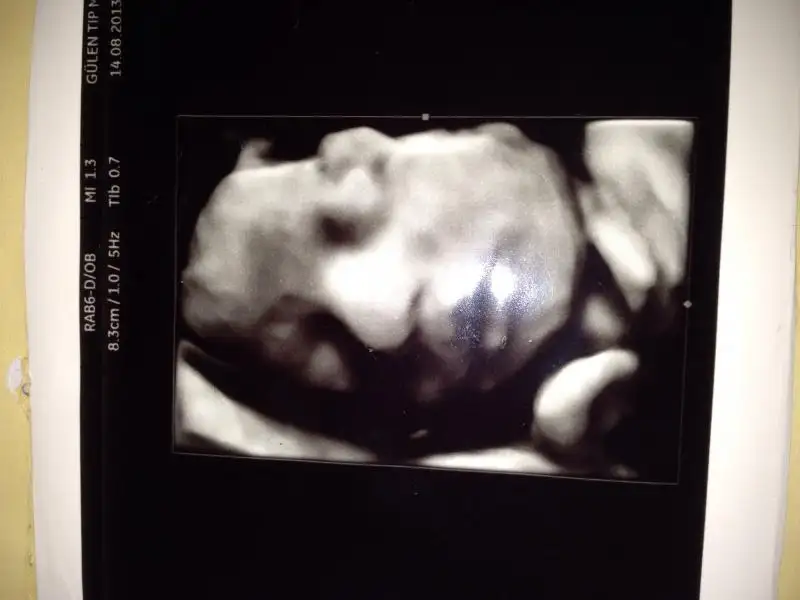

oyy suna bak ya zulummm kime benziyooo :52::52: Biz suratini bile gormedik bize tam supriz yapicak:27::27:

Bana benziyor tatlım:1: